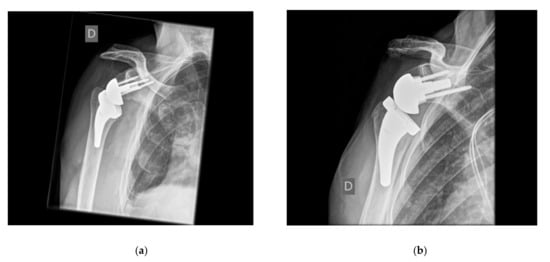

4. Lateralization (Global)

4.1. Glenoid Lateralization

4.1.1. Advantages of Glenoid-Sided Lateralization

4.1.2. Possible Negative Effects of Glenoid-Sided Lateralization

4.1.3. Technical Limitations to Metal-Augmented or Bony Lateralization

4.2. Humeral Lateralization

4.2.1. Advantages of Humeral Lateralization

4.2.2. Disadvantages of Isolated Humeral Lateralization